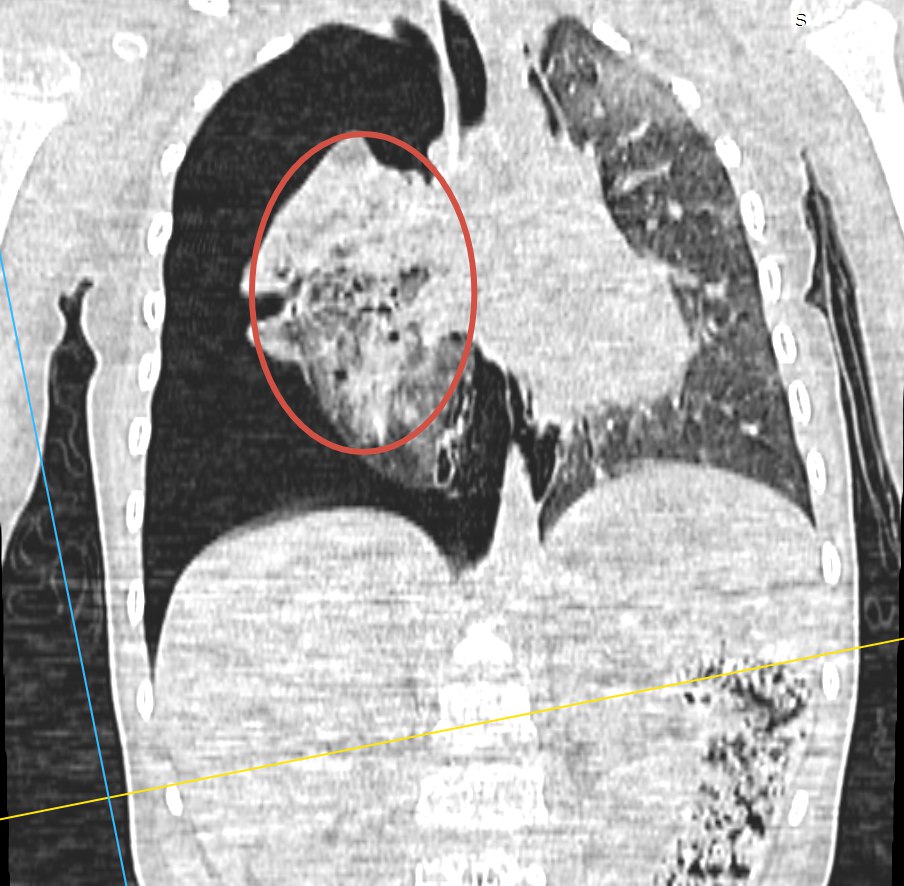

Результаты КТ:

• массивный правосторонний пневмоторакс с коллабированием более 2/3 правого лёгкого (на иллюстрации — повреждённое лёгкое, сжатое до размера апельсина)

• гемоторакс справа

• пневмомедиастинум

• ушиб обоих лёгких средней степени тяжести

• данных за продолжающееся кровотечение нет

• повреждений костей, черепа, лицевого скелета и головного мозга не выявлено

• повреждений органов брюшной полости не выявлено